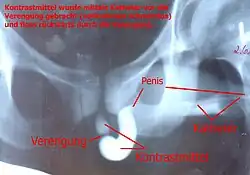

Am Anfang stehen eine genaue Befragung (Anamnese) des Patienten und die Uroflowmetrie. Hierbei ist insbesondere auf die Dauer der Beschwerden, Verletzungen und Infektionen zu achten. Eine Urinuntersuchung zur Infektdiagnostik ist ebenfalls zwingend erforderlich. Die Sonografie gibt Auskunft über die Restharnmenge, den Zustand der Harnblase, hier vor allem die Dicke der Blasenwand und die Nieren. Zur Lokalisation der Striktur ist eine Röntgenuntersuchung mit Kontrastmittel erforderlich. Bei dieser so genannten retrograden Urethrografie wird Kontrastmittel in die gestreckte Harnröhre gespritzt und gleichzeitig durchleuchtet. Hierbei können der Ort und die Länge der Striktur bestimmt werden. Ist hier keine klare Aussage möglich, kann sich noch eine Spiegelung der Harnröhre anschließen (Urethroskopie).